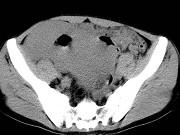

问题 男,23岁,下腹部肿块伴持续性钝痛1月余,影像所见如图,最可能的诊断是()

选项 A.小肠淋巴瘤 B.小肠间质瘤 C.小肠癌 D.小肠转移瘤 E.小肠结核

答案 A